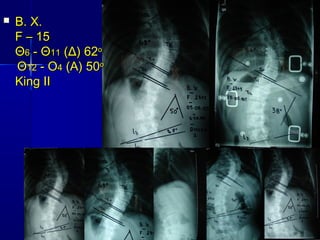

61. Β. Χ.Β. Χ.

F –F – 1515

ΘΘ66 - Θ- Θ1111 (Δ) 62(Δ) 62οο

ΘΘ1212 - Ο- Ο44 (Α) 50(Α) 50οο

King IIKing II